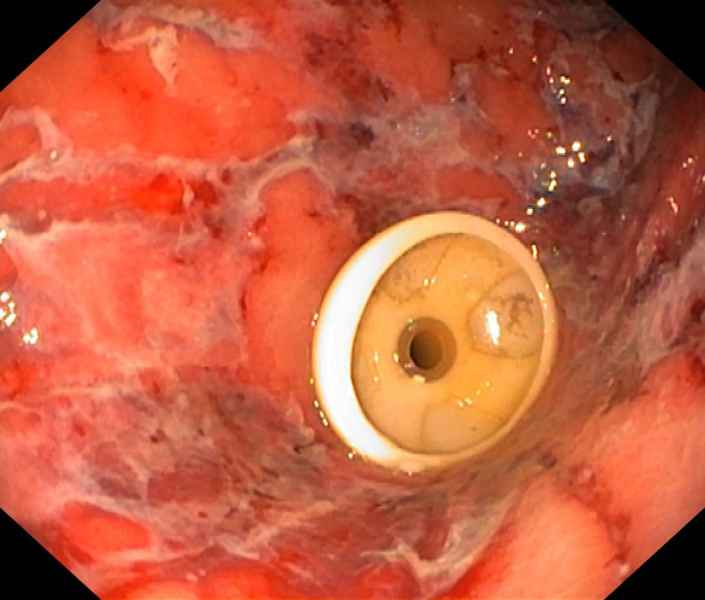

Rupture under the bridge, which way should I go?

Fotografia